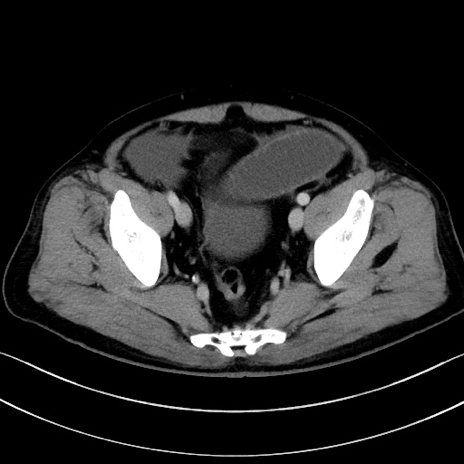

症例15(横断像)

【症例】70歳代男性

【主訴】腹痛

【現病歴】今朝から腹痛あり。全体的に痛い。特に左上の方。排ガスが今日はない。冷や汗が出る。

【既往歴】直腸癌術後

【身体所見】左側腹部〜上腹部に圧痛あり。腹膜刺激症状明らかなではない。軽度反跳痛。左下腹部に術後瘢痕あり。

【データ】WBC 7700、CRP 0.02